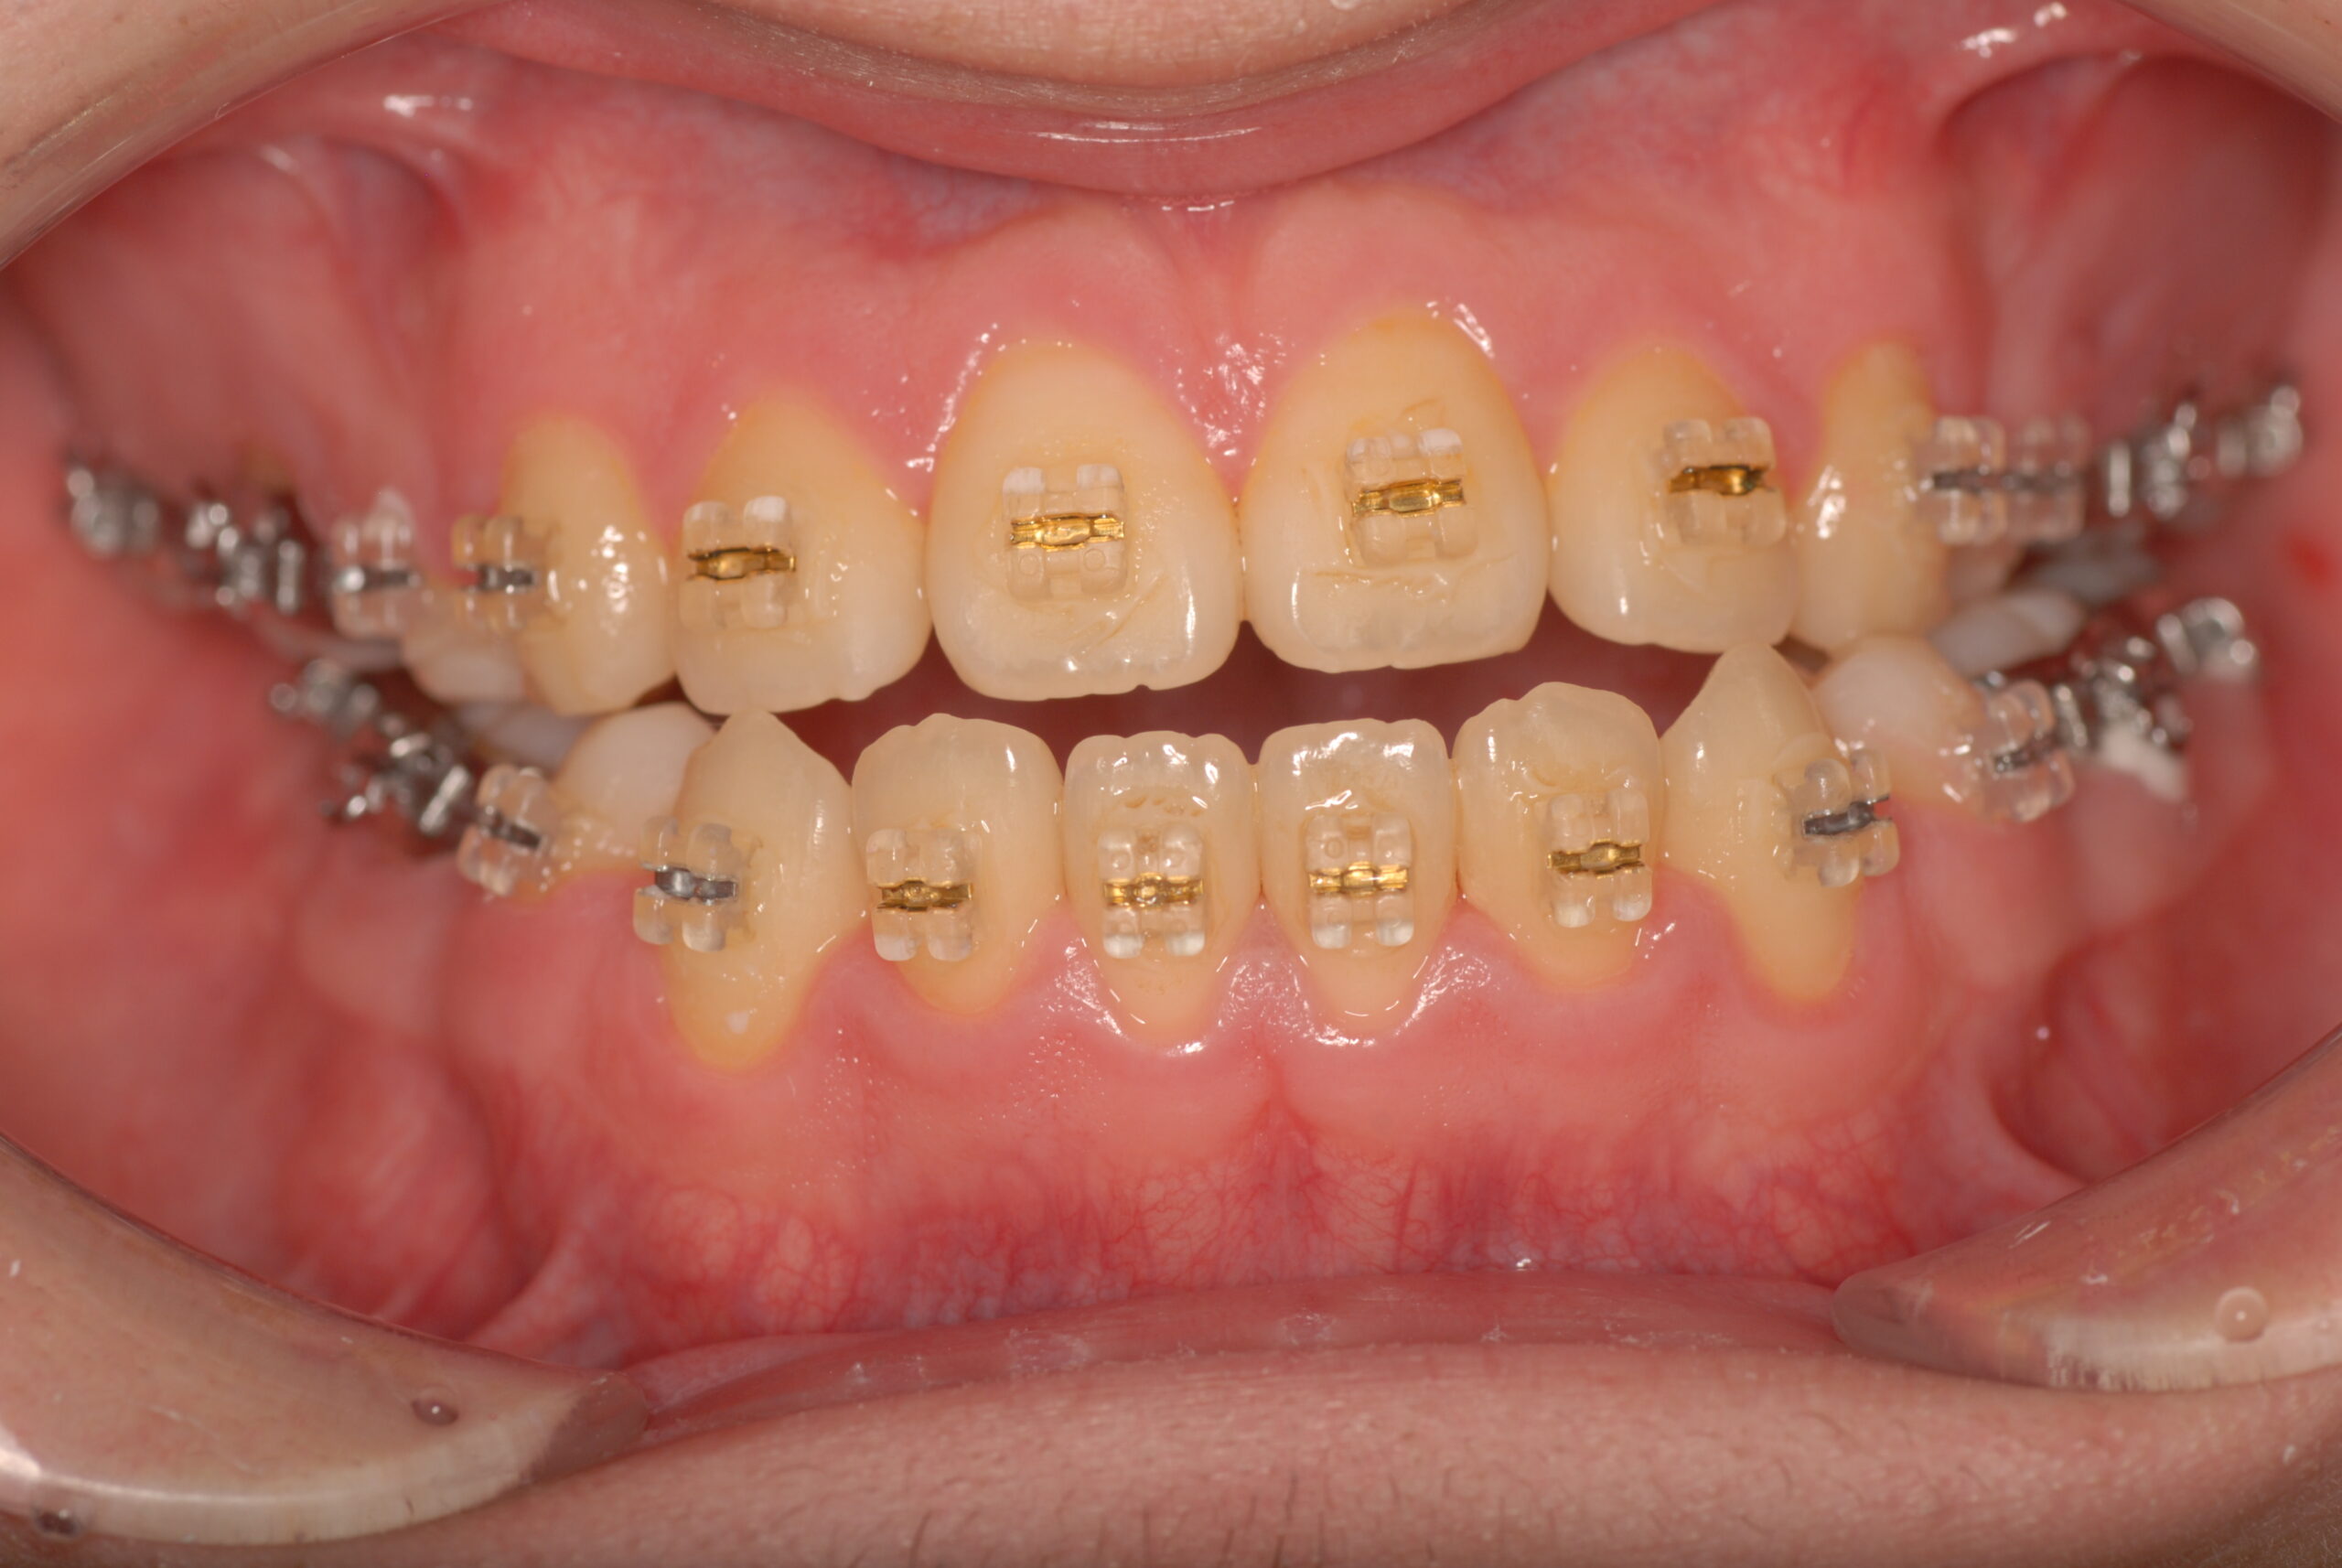

Progress

- 骨格性下顎前突症、下顎骨左偏位、叢生、 顎変形症として、外科的矯正術を計画。 叢生、右側第2大臼歯鋏状咬合。 上下顎第一小臼歯を抜歯し、抜歯空隙を利用し叢生を改善し、上下顎それぞれ歯列を整列し、矯正治療中に病院歯科口腔外科にて外科手術(近郊の病院歯科口腔外科にて、口の中から手術、2週間入院)により下顎骨の後退と左偏位の改善をし、適切なオーバージェット、オーバーバイトを付与する。